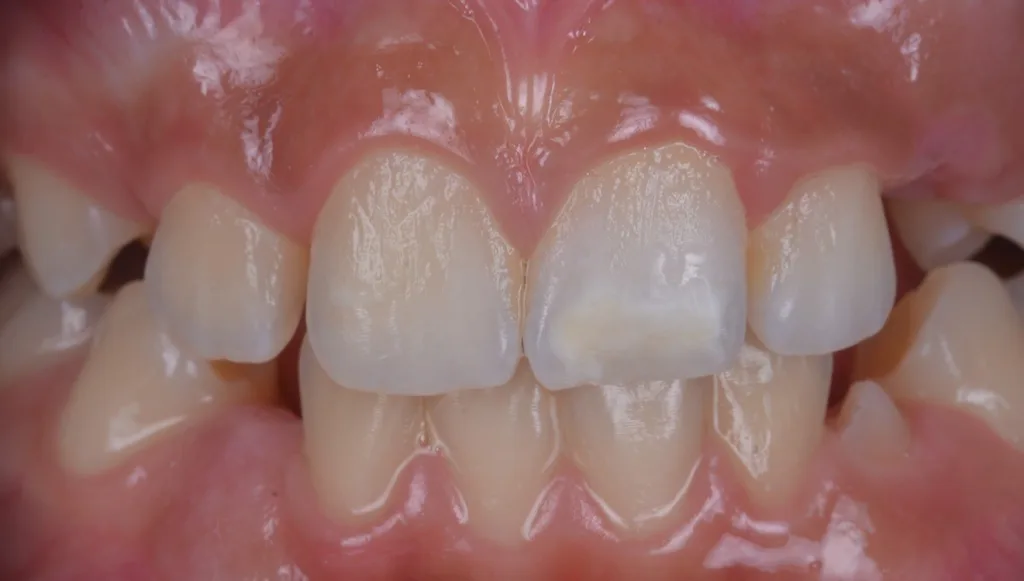

MIH-Läsionen an den Frontzähnen manifestieren sich häufig als klar abgegrenzte Opazitäten, deren Farbpalette von Weiß über Creme und Gelb bis hin zu Braun reicht. Diese farblichen Veränderungen sind ein wichtiger diagnostischer Hinweis auf die zugrundeliegende Strukturstörung des Zahnschmelzes. Besonders auffällig ist, dass die Intensität der Färbung mit dem Grad der Porosität und der strukturellen Beeinträchtigung des Schmelzes korreliert: Je dunkler und ausgeprägter die Opazität erscheint, desto höher der Restproteingehalt im Zahnschmelz, und desto höher ist das Risiko für posteruptive Substanzverluste, Frakturen und Hypersensitivitäten (Abb. 1). Die sorgfältige Beurteilung dieser visuellen Merkmale ist daher von zentraler Bedeutung für die Planung einer individuellen und effektiven Therapie, die sowohl funktionelle als auch ästhetische Aspekte berücksichtigt.

Um diesen Herausforderungen zu begegnen, wurden verschiedene modifizierte Behandlungsprotokolle entwickelt. Diese beinhalten unter anderem die Verlängerung der Infiltrationszeiten, das gezielte Abtragen der Oberflächenschicht (idealerweise als „selective surface removal“ unter Transilluminationskontrolle), um den Zugang des Infiltranten zum Läsionskörper zu ermöglichen, sowie eine Vorbehandlung mit oxidierenden Substanzen, um die Durchlässigkeit des Schmelzes für den Infiltranten zu steigern [17,18]. Darüber hinaus hat sich die optische Kontrolle der Infiltration mittels Transillumination als hilfreiches Instrument erwiesen, um den Infiltrationserfolg in Echtzeit besser beurteilen zu können und die Behandlung entsprechend anzupassen [17] (vgl. Fallbeispiel in Abb. 2).

![Abb. 2: Klinisches Fallbespiel [17]: a) Klinischer Ausgangbefund bei einem 12-jährigen Patienten,](https://dentalwelt.spitta.de/wp-content/uploads/2026/04/Abb2_A-1024x707.webp)